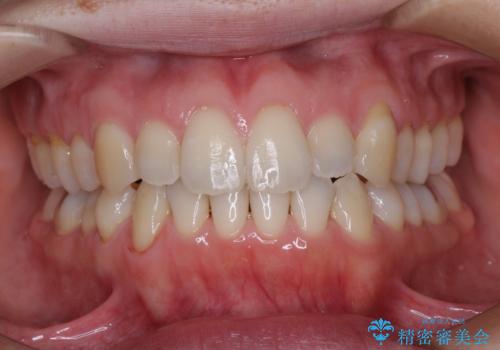

- 1年6ヶ月

- 10-30回

下顎の骨格的なズレが大きかったため、上下歯列のバランスが取れるか心配でしたが、上下ともに左右対称に近い歯列で治療を終えることができました。